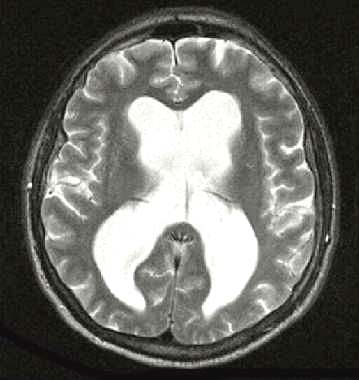

МР-томограмма при внутричерепной гипертензии

Гипертензивный церебральный криз диагностируется терапевтом, неврологом или кардиологом на основании типичной клинической картины, данных о развитии имеющейся симптоматики и измерения АД. Дополнительные инструментальные исследования обычно проводятся после оказания пациенту неотложной помощи и направлены на углубленную диагностику состояния мозгового кровообращения и сердечно-сосудистой системы. Они могут включать ЭКГ, суточный мониторинг АД, реоэнцефалографию, Эхо-ЭГ, ЭЭГ, УЗДГ сосудов головы, консультацию офтальмолога, офтальмоскопию, периметрию, МРТ головного мозга.